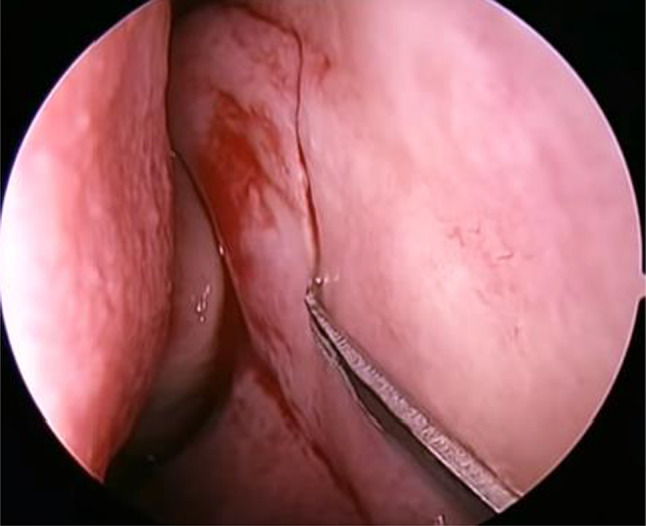

I. Incision and Flap ElevationIncision was made in the lateral wall of the nose with the assistance of a sickle knife, beginning at 5 mm posterior to the insertion of the middle turbinate and 10 mm above the axilla, and then proceeding vertically downwards. The inferior limit of the flap was 10 mm anterior to the uncinate and just at the superior margin of the inferior turbinate and so posteriorly based flap elevated from maxillary bone extending up to the uncinate process (Fig. 2)

Fig. 2.

Incision over the lateral nasal wall for elevation of posteriorly based mucosal flap